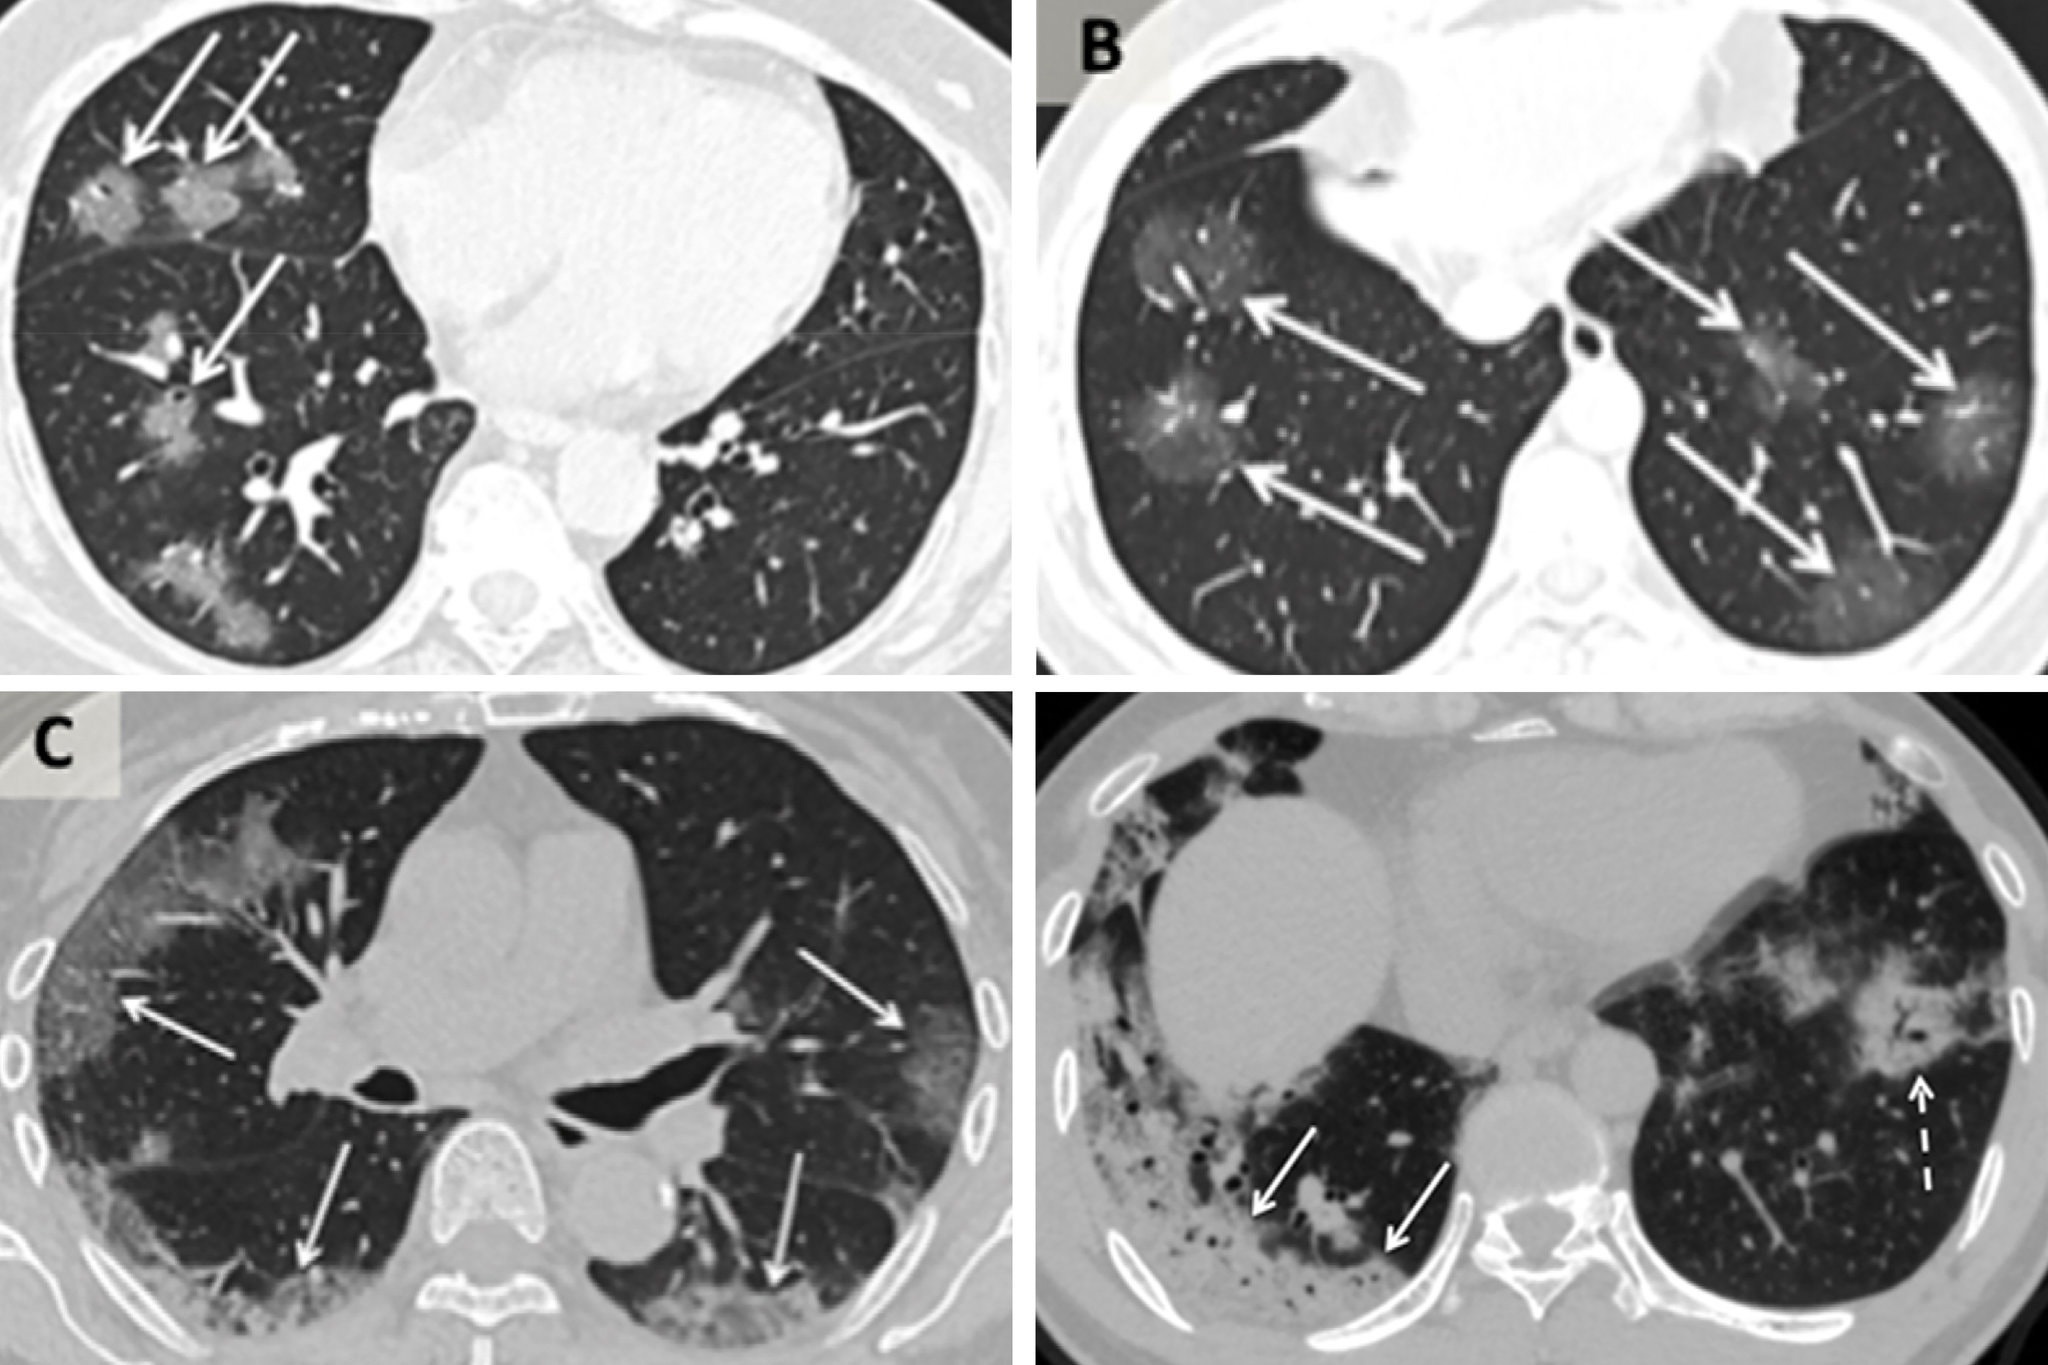

virus corona anh 3

Ảnh chụp CT của các bệnh nhân Trung Quốc bị nhiễm virus corona. Theo chiều kim đồng hồ từ trên cùng bên trái, một phụ nữ 56 tuổi, một nam 44 tuổi, một nam 42 tuổi và một nữ 65 tuổi.

Nghiên cứu này và nghiên cứu của bác sĩ Xiao cho thấy khi bệnh tiến triển, ảnh CT cho thấy "các vệt thủy tinh mờ", một loại màng che ở các bộ phận của phổi có thể thấy rõ trong nhiều loại bệnh nhiễm trùng đường hô hấp do virus.

Những khu vực mờ đục đó có thể phân tán và dày lên khi bệnh nặng hơn, tạo ra thứ mà các bác sĩ chụp X-quang gọi là màng bao dày đặc trên máy quét.